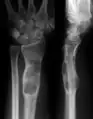

| X-ray image showing enchondromas localized in the lower part of the radius of a 7-year-old girl with Ollier disease. | |

Abnormal bone growth such as shortening or thickening and deformity may be observed in patients of Ollier disease. These bone lesions are visible at birth using radiography but are usually not screened or examined for until clinical manifestations present during early childhood. However, some patients may exhibit no signs of any symptoms.[1] One study found thirteen to be the mean age of diagnosis in patients with Ollier disease. In an X-ray, there would normally be the presence of several homogeneous lesions of an oval or elongated shape with bone edges that are slightly thickened.[3] With age, these lesions may calcify and appear as diffusely minute spots or stippled. Fan-like septations or streaks would be indicative of the presence of several enchondromas. Early detection and consistent and repeated monitoring is important in order to prevent and treat any potential bone neoplasms.